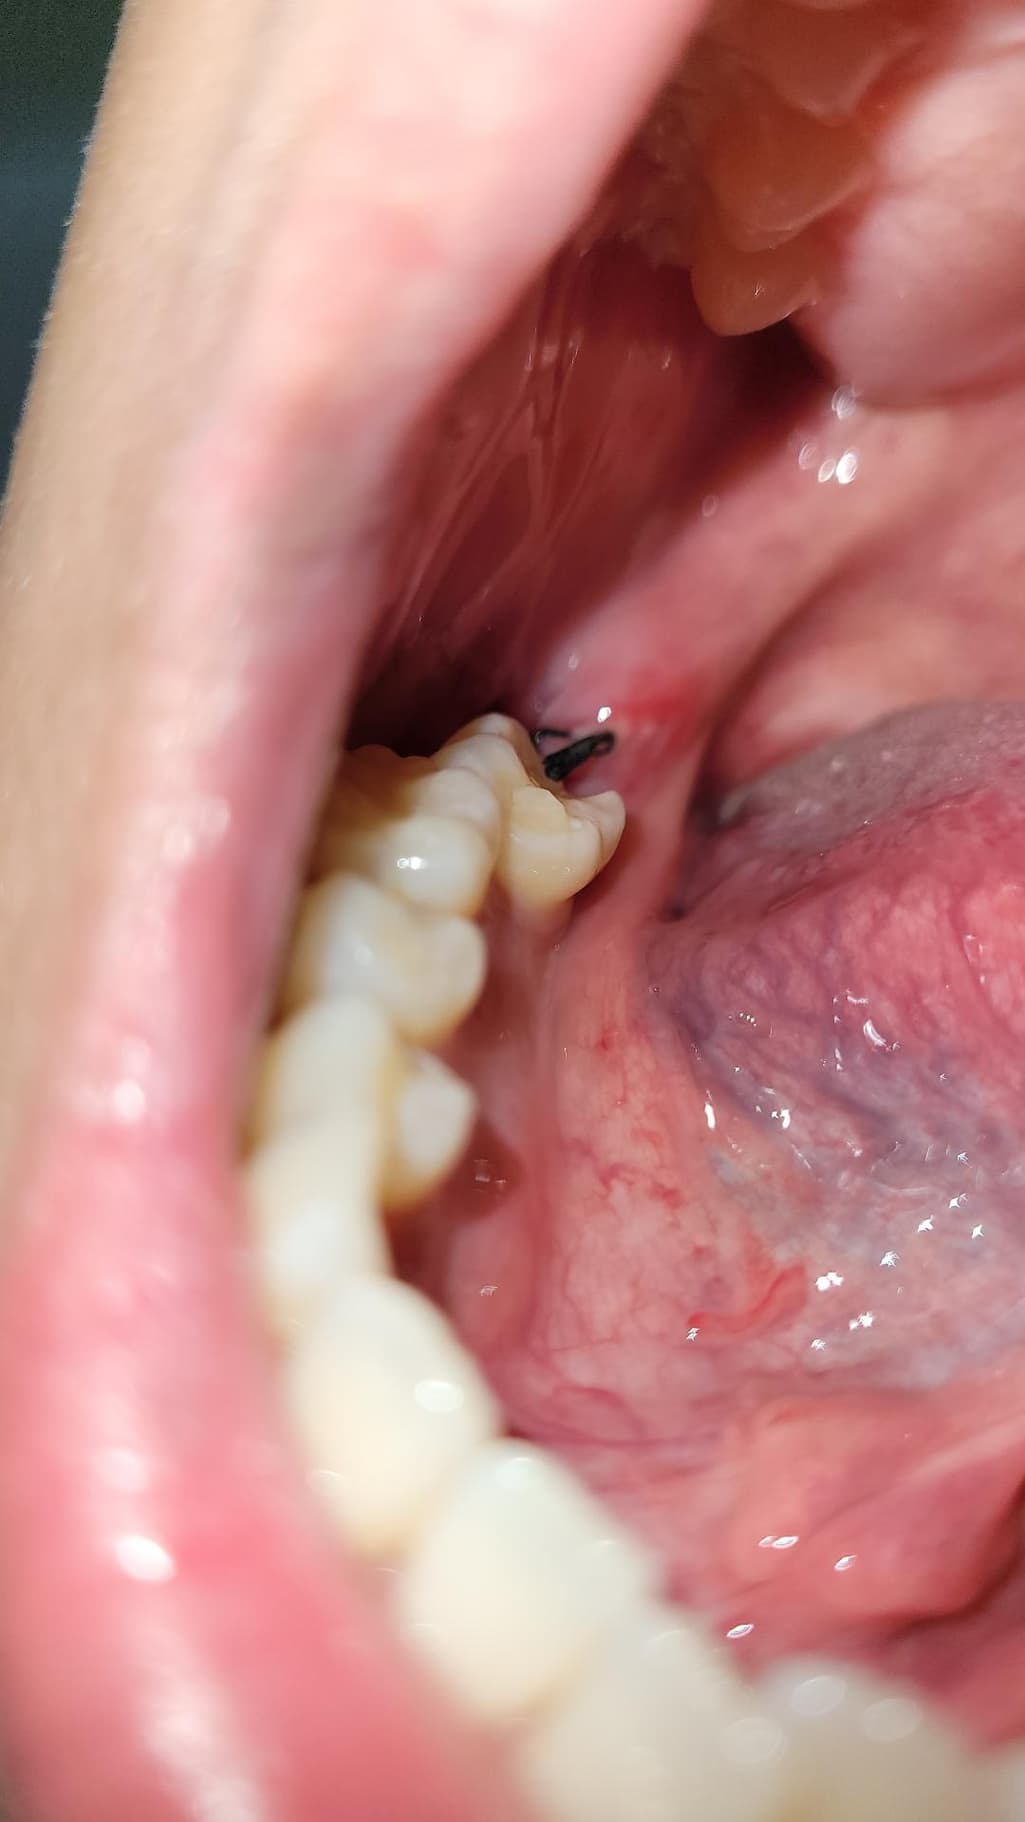

이거 혹시 드라이소켓 같은건가요?? 실밥이 풀린건가요...

이게 실밥이 풀린건지 안에 흰색이 보여서 그러는데 이게 멀까요... 아 진짜 사랑니 뽑은지는 3일 됐는데 바로 치과 가야할까요?? 아니면 어떡해야할까요

하얀색은 잇몸이 치유되는 조직으로 보이고, 실밥은 느슨해진 상태입니다. 드라이소겟은 참을수 없는 통증이 동반됩니다. 염려가 된다면 치과에 내원하여 소독을 받는것도 좋을것 같습니다. 건강하세요.

흰색 보이는 건 치유과정에서 생기는 염증,육아조직 같습니다

실밥은 밥먹다가, 양치하다가 지연스럽게 풀리기도 합니다